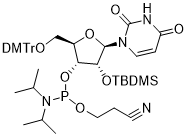

馬鞍山致研生物醫(yī)藥科技有限公司成立于馬鞍山市鄭浦港新區(qū)現(xiàn)代產(chǎn)業(yè)園。公司專(zhuān)注于生物小分子、醫(yī)藥中間體相關(guān)產(chǎn)品的研發(fā)和生產(chǎn),產(chǎn)品主要包括DNA亞磷酰胺單體、RNA亞磷酰胺單體、特殊單體以及按照客戶(hù)要求定制的RNA和DNA,并且公司提供定制合成等方面的研究服...

馬鞍山致研生物醫(yī)藥科技有限公司成立于馬鞍山市鄭浦港新區(qū)現(xiàn)代產(chǎn)業(yè)園。公司專(zhuān)注于生物小分子、醫(yī)藥中間體相關(guān)產(chǎn)品的研發(fā)和生產(chǎn),產(chǎn)品主要包括DNA亞磷酰胺單體、RNA亞磷酰胺單體、特殊單體以及按照客戶(hù)要求定制的RNA和DNA,并且公司提供定制合成等方面的研究服...